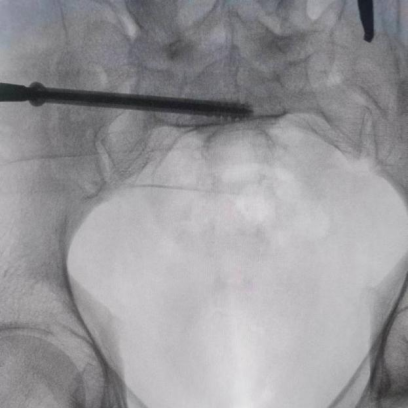

圖為吳宏華主任術中于健側髂后上級置入信號收集裝置

圖為透視下見置入的骶髂螺釘,位置、長度精準,無絲毫偏差